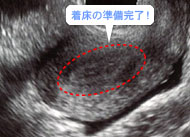

細長い輪のように見えるのが、子宮内膜。厚みを増して受精卵を待っています。(妊娠3週)

妊娠2週末~3週初め、子宮にたどり着いた受精卵は子宮内膜にぴったりくっついたあと、外側の膜が破れて子宮内膜の中へ入り込みます。これが着床!妊娠の成立です。